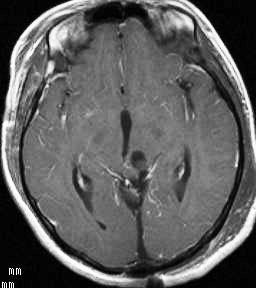

左は術前,右は手術直後のMRIです。このビデオを見て,およその手技の順番のみ把握して下さい。